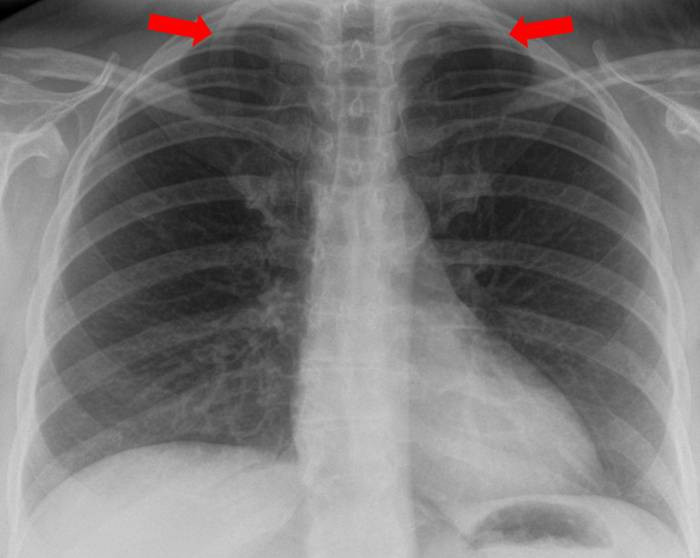

3 Hinweise zur Befundung / ILOKlassifikation von digitalen Radiografien des Thorax A) Definition Befundung Nach den Richtlinien zur Durchführung der Qualitätssicherung bei Röntgeneinrichtungen aus dem Jahr 03 (QSRL) zur Untersuchung und Behandlung von Menschen nach §§ 16, 17. Diese Seite wird in Browsern angezeigt, die Rahmen nicht unterstützen Bearbeiten Sie diese Seite in diesem Modus, um sie für solche Browser anzupassen Für Browser, die Rahmen. Der RöntgenThorax kann Hinweise auf die zugrundeliegende Ursache der Trachealstenose liefern Zum Beispiel können eine Trachealdeviation, eine Mediastinalverbreiterung oder andere Ursachen für Kurzatmigkeit wie eine Aspiration eines Fremdkörpers erkennbar sein Die Abbildung zeigt den RöntgenThorax eines Patienten mit vergrößerter.